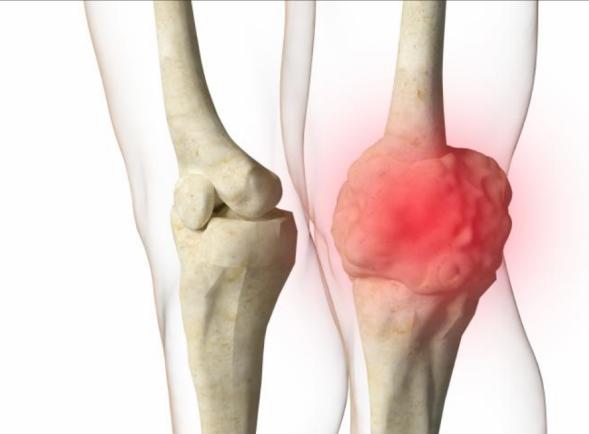

2.好发部位:多见于膝关节周围,也就是股骨远端、胫骨近端,肱骨近端也较为常见,肩关节也可能受累。这些部位都是长骨的干骺端,是骨骼生长最活跃的区域,骨肉瘤的发生和骨骼快速生长有密切关联。

2.局部肿块:肿瘤部位会出现质地坚硬的肿块,生长速度较快,局部皮肤温度升高,还可能看到表面血管凸起;